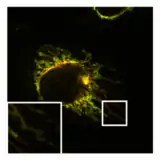

In addition to this inhibition of the function of mitochondria, PXA also disrupts their membrane architecture. In many cell types, the mitochondria normally form an intricate tubular network that undergoes a constant process of balanced mitochondrial fission and mitochondrial fusion. Treatment with PXA or many other mitochondrial stressors, such as protonophores, causes excessive fission that results in mitochondrial fragmentation. In the case of PXA, however, this fragmentation process was shown to be different from canonical fragmentation, caused by other agents such as protonophores, in several ways: first, it is considerably faster, resulting in complete fragmentation within a minute as opposed to about 30–60 minutes for canonical fragmentation; second, it is independent from the mitochondrial fission and fusion regulators DRP1 and OPA1; and third, while PXA causes fragmentation of both the outer mitochondrial membrane (OMM) and the mitochondrial matrix in wild type cells, it causes exclusive fragmentation of the matrix in cells that lack DRP1.[1] This last feature is especially unusual since no active mechanism for exclusive matrix fission is known in higher eukaryotes.[12] Examination of the mitochondrial ultrastructure revealed that PXA causes cristae disruption and complete distortion of the mitochondrial matrix. It is probably through this effect that PXA induces programmed cell death in the form of apoptosis.[1]

Normal, tubular morphology of mitochondria in a HeLa cell in which the fission mediator DRP1 has been knocked out. Overlay image of mitochondrial matrix (green) and OMM (red).

Normal, tubular morphology of mitochondria in a HeLa cell in which the fission mediator DRP1 has been knocked out. Overlay image of mitochondrial matrix (green) and OMM (red).